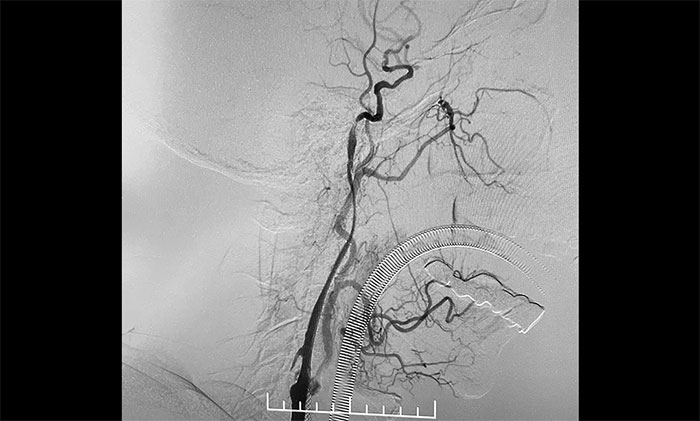

術(shù)中,超滑導(dǎo)絲、多功能導(dǎo)管經(jīng)過反復(fù)嘗試順利通過左頸內(nèi)動(dòng)脈起始段,到達(dá)左頸內(nèi)動(dòng)脈遠(yuǎn)端顯影段,路圖見遠(yuǎn)端血管通暢,左大腦中動(dòng)脈顯影;隨后,微導(dǎo)絲經(jīng)多功能導(dǎo)管置于左頸內(nèi)動(dòng)脈海綿竇段,經(jīng)微導(dǎo)絲送入保護(hù)傘至左頸內(nèi)動(dòng)脈巖骨垂直段并釋放,再沿保護(hù)傘微導(dǎo)絲送入4x30mm球囊于左頸內(nèi)動(dòng)脈起始段,給予球囊擴(kuò)張,撤除球囊后造影見左頸內(nèi)動(dòng)脈起始段再通,左頸內(nèi)動(dòng)脈、左大腦中動(dòng)脈顯影;最后,送入9x50mm支架,釋放于左頸內(nèi)動(dòng)脈頸段至左頸總動(dòng)脈末段,造影見左頸內(nèi)動(dòng)脈起始段顯影明顯改善,左頸內(nèi)動(dòng)脈、左大腦中動(dòng)脈、左大腦前動(dòng)脈顯影可,行3D造影見左頸內(nèi)動(dòng)脈頸段顯影改善。行支架CT見支架成形可,行XperCT未見顱內(nèi)出血。

▲ 左側(cè)頸內(nèi)動(dòng)脈閉塞順利開通

手術(shù)圓滿完成,席剛明教授團(tuán)隊(duì)、麻醉科團(tuán)隊(duì)及導(dǎo)管室團(tuán)隊(duì)通力合作,耐心、仔細(xì)地克服了手術(shù)的所有難點(diǎn)。左頸內(nèi)動(dòng)脈從“無”到“有”,正所謂“精誠(chéng)所至,金石為開”,順利為患者解除危機(jī)。